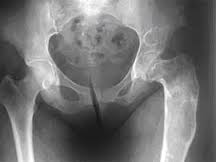

دیسپلازی فیبرو (Fibrous Dysplasia) یک تومور استخوانی خوش خیم است که قبل از تولد و به دلیل یک نقص ژنتیکی در سلول های سازنده استخوان ایجاد و شروع میشود که در دوران نوزادی بی علامت و اغلب در دوران کودکی و نوجوانی و یا حتی بزرگسالی مشخص میشود. دیسپلازی فیبرو اغلب در یک استخوان دیده میشود ولی گاهی در استخوان های متعددی در بدن ایجاد میشود.

بر اثر یک نقص ژنتیکی در دیسپلاژی فیبرو استخوان طبیعی و سالمی ساخته نشده و استخوان در بعضی نواحی بدن ضعیف و پوک است. این نقصان در کل اسکلت بصورت پراکنده وجود داشته و میتواند موجب درد یا شکستگی و یا تغییر شکل استخوان ها شود. این عارضه در هر استخوانی میتواند بروز کند ولی در ران، ساق، بازو، لگن، جمجمه و دنده شایعتر است.